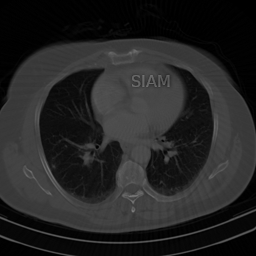

Fig. 2 presents an example of this result. In this figure, the ‘Mickey Mouse’ detail , whereas the ‘Thumb’ detail has relatively large measurements, i.e., . The NN is trained to recover the image . As a result, it incorrectly transfers the detail , while the detail is handled correctly (i.e., it is not transferred). Fig. 4 shows another example of this effect. In this case, is a subsampled Radon transform, which models a CT imaging scenario. Here, the NN is trained to recover the detail image , and as a result, it incorrectly transfer the detail when recovering the detail-free image .

|

\begin{overpic}[width=433.62pt]{plots/sample_00101_pred.png} \put(45.0,82.0){\color[rgb]{1,0,0}\definecolor[named]{pgfstrokecolor}{rgb}{1,0,0}\vector(1,-2){6.0}} \end{overpic} |

A.4 Fig. 4

In Fig. 4, we trained a NN to reconstruct CT images from Radon measurements. For the sampling operator, we used MATLAB’s implementation of the Radon transform, and sampled 50 equally spaced angles. The choice of considering 50 angles is inspired by the seminal work of Jin, McCann, Froustey & Unser in [40]. As we considered images with dimensions , the sampling operator had dimensions and .

In this experiment we used the 100 CT images from the cancer imaging archive [5, 20] that have been made available at kaggle.com (See: https://www.kaggle.com/datasets/kmader/siim-medical-images/). Due to the small size of this dataset, we trained the NN in two stages. In the first stage, we pretrained the NN on the 25000 ellipses images used to train the NNs in Fig. 5. Then we fine-tuned the NN on 95 CT images from the dataset mentioned above. Among the 95 images used for training was the image , where is the “SIAM” detail seen in the image. The clean image was not part of the training data. The detail was designed such that . Specifically, we computed as , where is the identity matrix, and is a black image with the “SIAM” text feature.

The architecture of the trained NN can be written as , where is a learnable U-Net and is the matrix of a (non-learnable) Filtered Backprojection (FBP) with a “Ram-Lak”-filter. The “Ram-Lak”-filter was chosen as it is the default filter in MATLAB. We trained the network for 60 epochs in the pretaining phase and for 520 epochs in the fine-tuning phase. We used a larger number of epochs in the fine-tuning phase than in the pretraining phase, as the amount of training data was substantially smaller in the fine-tuning phase. During all training epochs we used a mean-squared-error loss function and noiseless measurements.